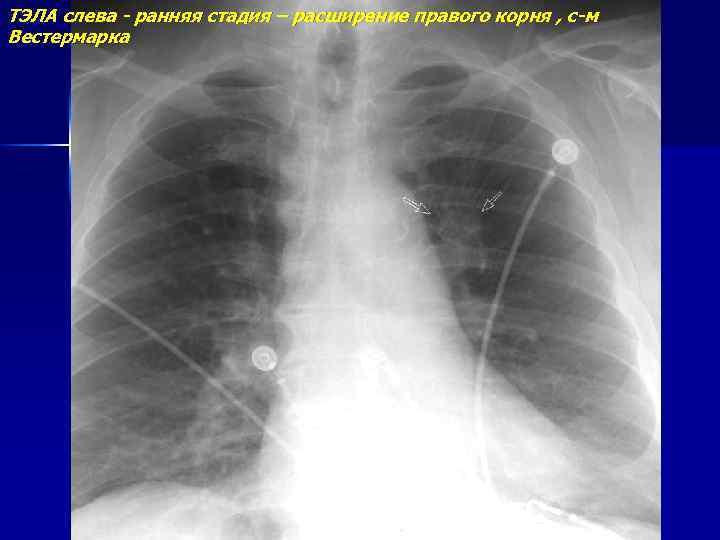

ТЭЛА слева - ранняя стадия – расширение правого корня , с-м Вестермарка

ТЭЛА слева - ранняя стадия – обеднение сосудистого рисунка в нижней доле слева